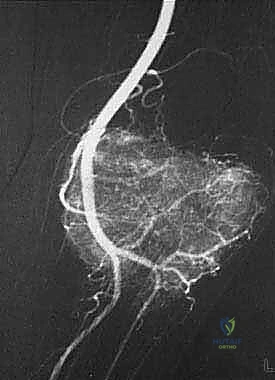

المرحلة الأولى: استئصال الورم (Resection)

يتم فتح الجلد والأنسجة بعناية فائقة. التحدي الأكبر هنا هو فصل الورم عن الأوعية الدموية والأعصاب الرئيسية المغذية للطرف. يستخدم الدكتور هطيف تقنيات الجراحة الميكروسكوبية لضمان سلامة هذه الهياكل الحيوية، مما يحافظ على حيوية الطرف وحركته.

- الجراحة الميكروسكوبية (Microsurgery): لخياطة الأوعية الدموية والأعصاب الدقيقة التي لا تُرى بالعين المجردة، مما يضمن تدفق الدم للطرف بعد الاستئصال الواسع.